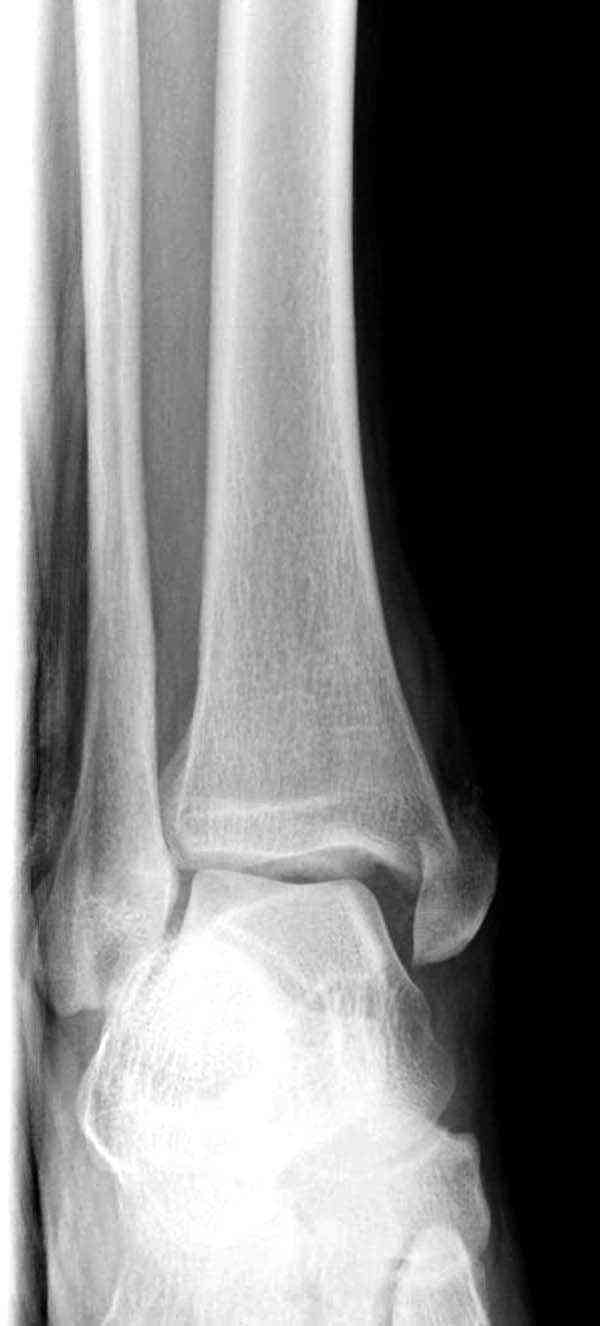

Нет первичных снимков, перелом очень низкий и под большим сомнением диагноз разрыва синдесмоза. Медиальная сторона отрепонирована на "хорошо" и, по-видимому, прорезание проволоки произошло во время операции. Без снимков трудно судить о высоте малоберцовой, а лодыжка находится в варусе. Лагирование получилось, но возле тонких шурупов передне-задний шуруп выглядит немного тяжеловато.

Медиальная лодыжка фиксируется каннюлированными лодыжечными шурупами перкутанно, а неточная репозиция (интерпозиция) является показанием к открытой технике. При больших вертикальных фрагментах нужны противоскользящие медиальные пластины.

Здесь несколько частных случаев: перелом голеностопа со сравнительными снимками и разрыв синдесмоза, а также медиальная Hook пластина.